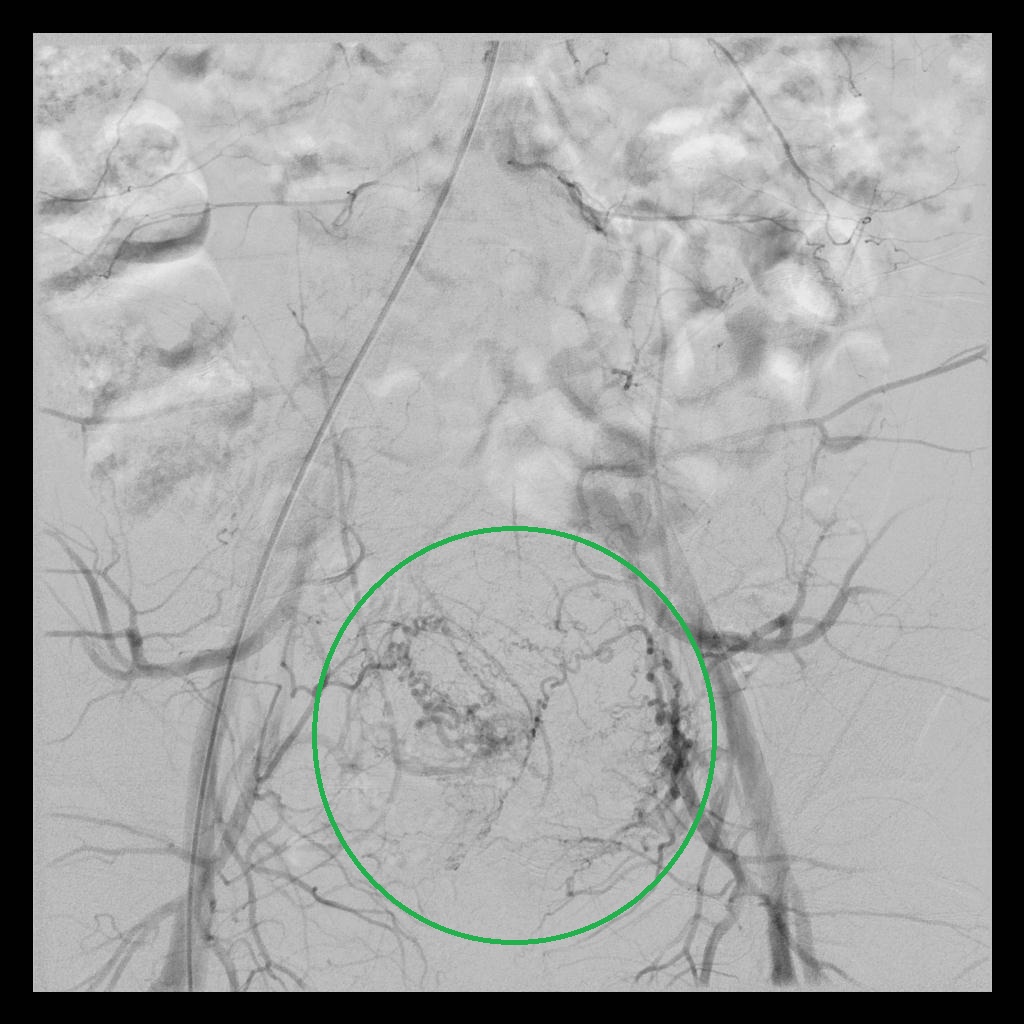

后经腹部主动脉造影显示,子宫双侧的子宫动脉均有增粗、迂曲的情况(下图中红色箭头所示),子宫和子宫肌瘤也均有所增大(下图中绿圈所示)

术后,经子宫动脉造影显示:之前增粗、迂曲、供血丰富的子宫动脉,经栓塞术后,血流基本停滞;之前增大的子宫和子宫肌瘤,经栓塞术后,其造影染色也已消失。